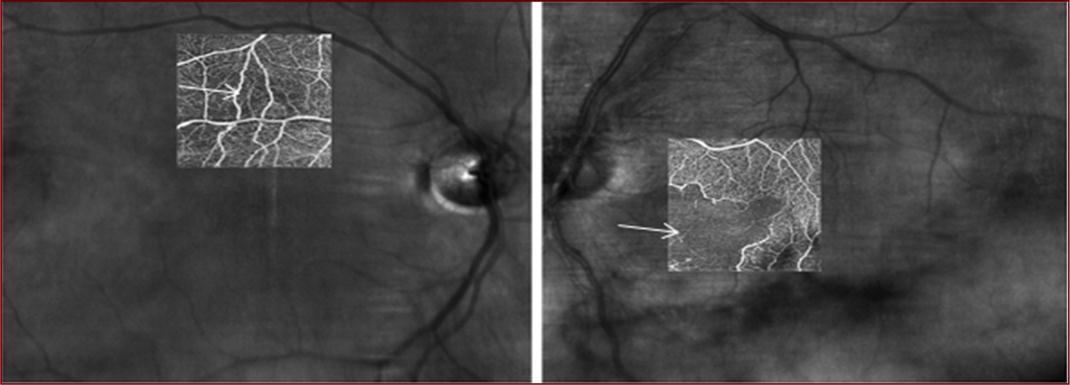

Image 3.Fluorescein angiography two months after first presentation showing mild capillary drop out in the right eye (arrow) and several arterial occlusions in the left eye (arrows).

Image 4.OCT angiography non-segmented images two months after first presentation showing mild loss of inner retinal perfusion of the right and severe loss of perfusion in the left eye (arrows).